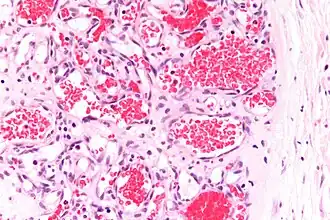

Capillary hemangioma

Strawberry naevus, H&E stain

A precise history of the growth characteristics of the IH can be very helpful in making the diagnosis. In the first 4 to 8 weeks of life, IHs grow rapidly with primarily volumetric rather than radial growth. This is usually followed by a period of slower growth that can last 6–9 months, with 80% of the growth completed by 3 months. Finally, IHs involute over a period of years.[36] The exceptions to these growth characteristics include minimally proliferative His, which do not substantially proliferate[35] and large, deep IHs in which noticeable growth starts later and lasts longer.[36] If the diagnosis is not clear based on physical examination and growth history (most often in deep hemangiomas with little cutaneous involvement), then either imaging or histopathology can help confirm the diagnosis.[33][37] On Doppler ultrasound, an IH in the proliferative phase appears as a high-flow, soft-tissue mass usually without direct arteriovenous shunting. On MRI, IHs show a well-circumscribed lesion with intermediate and increased signal intensity on T1- and T2-weighted sequences, respectively, and strong enhancement after gadolinium injections, with fast-flow vessels.[33] Tissue for diagnosis can be obtained via fine-needle aspiration, skin biopsy, or excisional biopsy.[38] Under the microscope, IHs are unencapsulated aggregates of closely packed, thin-walled capillaries, usually with endothelial lining. Blood-filled vessels are separated by scant connective tissue. Their lumina may be thrombosed and organized. Hemosiderin pigment deposition due to vessel rupture may be observed.[39] The GLUT-1 histochemical marker can be helpful in distinguishing IHs from other items on the differential diagnosis, such as vascular malformations.[34]